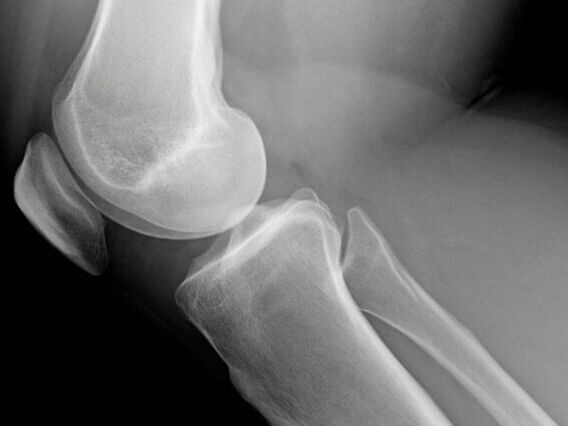

Uma das dores mais comuns relatadas em consultórios ortopédicos – a dor na frente do joelho – tem como principal causa a condromalácia patelar, que nada mais é que um amolecimento da cartilagem, ou seja, um desgaste.

Conhecida também com outros nomes como: a dor femoropatelar, a hipertensão patelofemoral, a condropatia patelar e a síndrome patelofemoral, a condromalácia patelar é consequência de uma sobrecarga mecânica na patela que, com o tempo, pode levar ao desenvolvimento de lesões na cartilagem articular e, aos poucos, a dores mais intensas.

A cartilagem que reveste a patela é uma das mais espessas do corpo, justamente para receber um excesso de força que habitualmente passa pela articulação. Quando a musculatura está fraca e o alinhamento da perna é perdido, porém, a força que o corpo dispende sobre a patela é muito maior. Se isso não for devidamente corrigido, poderão ocorrer lesões da cartilagem da patela.

Enquanto as lesões ainda são superficiais, a estrutura óssea não contribui para as dores, porém, ao atingir camadas mais profundas, a proteção oferecida pela cartilagem vai sendo perdida ao longo do tempo, piorando a dor e, possivelmente, contribuindo para o desenvolvimento de uma artrose no joelho.